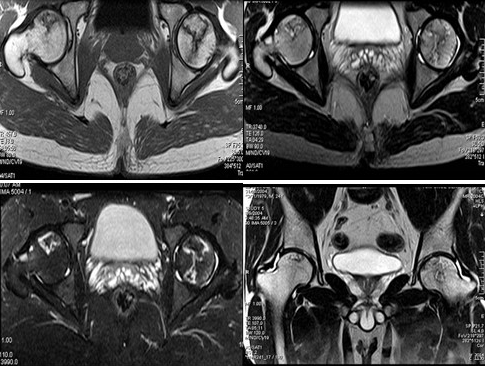

患者,男,24岁,曾有外伤史,两侧髋部疼痛不适数月,请结合所提供的图像,选择最佳答案()

A:股骨头无菌性坏死

B:髋关节退行性变

C:未见异常

D:化脓性骨关节炎

E:类风湿关节炎两侧